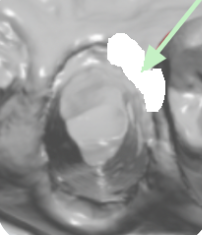

Uso de la herramienta de recorte

Si hay obstrucciones, elimínelas del escaneo utilizando la herramienta de recorte. Después de recortar, ajuste según sea necesario y vuelva a escanear el área. A continuación se muestra un ejemplo de los pasos que realizaría al usar la herramienta de recorte para tejido sobre un margen.

• Tejido sobre el margen

• Recortando el área afectada

• Colocación de cordón y reescaneo